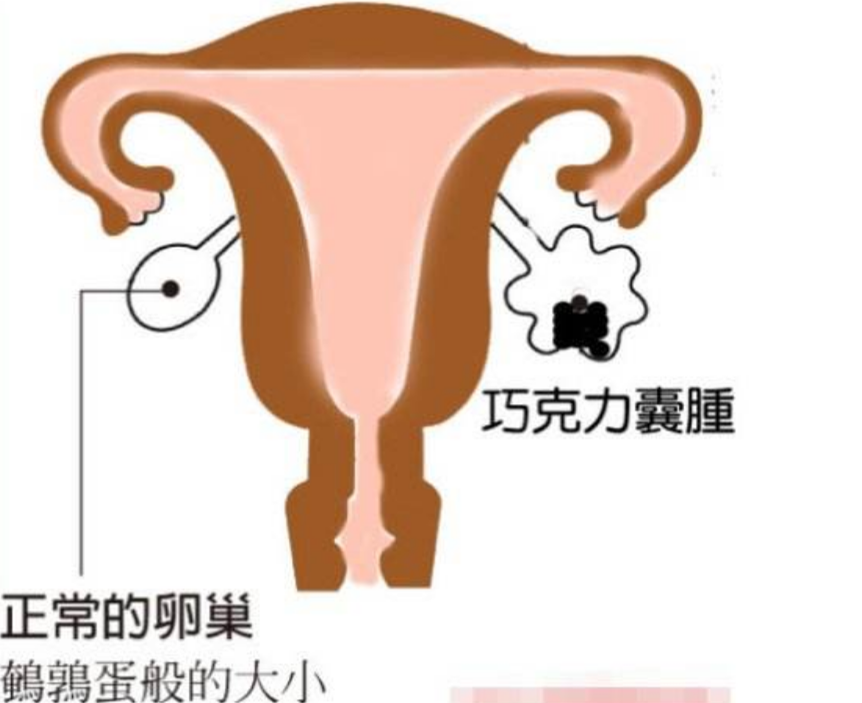

巧克力囊腫圖片

巧克力囊腫

什麼是巧克力囊腫

A:巧克力囊腫也就是卵巢子宮內膜異位囊腫,它是由於異位的子宮內膜在卵巢內生生長,隨著月經多次樣出血,形成了一個存在陳舊性的積血囊腫,囊腫內容物一般像巧克力狀,所以稱為巧克力囊腫。引起內膜異位囊腫的原因現在不清楚,有許多的學說,最常聽到的就是子宮……

A:卵巢巧克力囊腫是子宮內膜異位症的一種,子宮內膜異位症包括巧克力囊腫、盆腔子宮內膜異位結節,以及子宮腺肌症。卵巢巧克力囊腫是經血逆流導致,經期會有經血逆流,如果逆流的經血種植在卵巢表面,定期剝脫、出血,逐漸增大就會形成巧囊,這與女性的特殊體質……